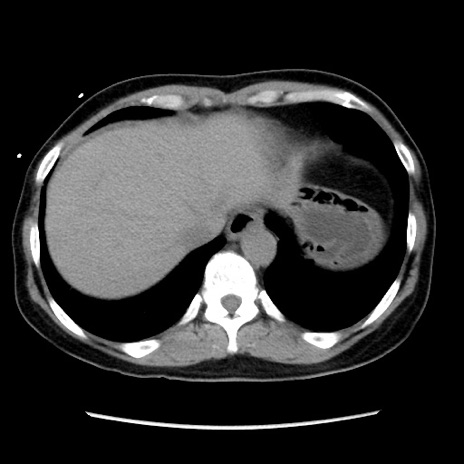

症例10(横断像)

【症例】 50歳代女性

【主訴】 腹痛

【現病歴】前日生レバーを食べた。今朝に排便あり。 昼前に突然発症の腹痛を生じ、当院救急外来を受診した。

【身体所見】 意識清明、腹部:平坦、軟、下腹部やや左を中心に圧痛・反跳痛あり、筋性防御あり

【データ】WBC 7800、CRP 0.07